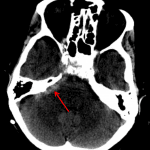

Age: 80

Sex: Female

Indication: Posttraumatic headache

- High density material layering in the left occipital horn and in the right cerebellopontine angle cistern, concerning for acute hemorrhage

- Partial opacification of the left mastoid air cells and middle ear

- Subtotal opacification of the left sphenoid sinus with intermixed high density material

- Trace intraventricular and subarachnoid hemorrhage

High density material layering in the left occipital horn and in the right cerebellopontine angle cistern, concerning for acute hemorrhage. No mass effect or hydrocephalus.

Left parieto-occipital scalp hematoma without subjacent calvarial fracture. Partial opacification of the left mastoid air cells and middle ear without definite temporal bone fracture. This finding could alternatively relate to inflammatory or infectious otomastoiditis.

Subtotal opacification of the left sphenoid sinus with intermixed high density material which may represent inspissated secretions or chronic fungal colonization.